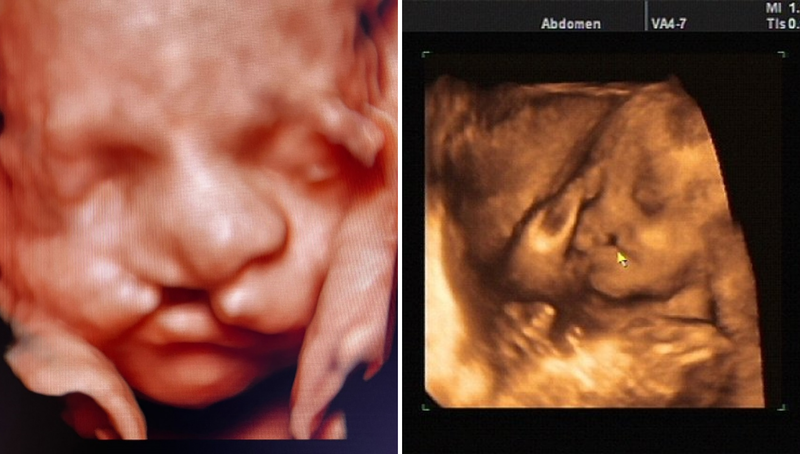

Hình ảnh siêu âm thai nhi bị hở hàm ếch thường cho thấy một khe hở ở môi trên hoặc vòm miệng. Trên siêu âm 2D, khe hở này có thể xuất hiện dưới dạng một đường đen giữa môi trên hoặc trong vòm miệng.

Siêu âm 3D và 4D cung cấp hình ảnh chi tiết hơn, giúp bác sĩ quan sát rõ ràng cấu trúc khuôn mặt của thai nhi và xác định mức độ nghiêm trọng của dị tật. Việc sử dụng siêu âm 3D có thể giúp phát hiện khe hở môi sớm hơn và cung cấp hình ảnh rõ ràng hơn về cấu trúc khuôn mặt của thai nhi.